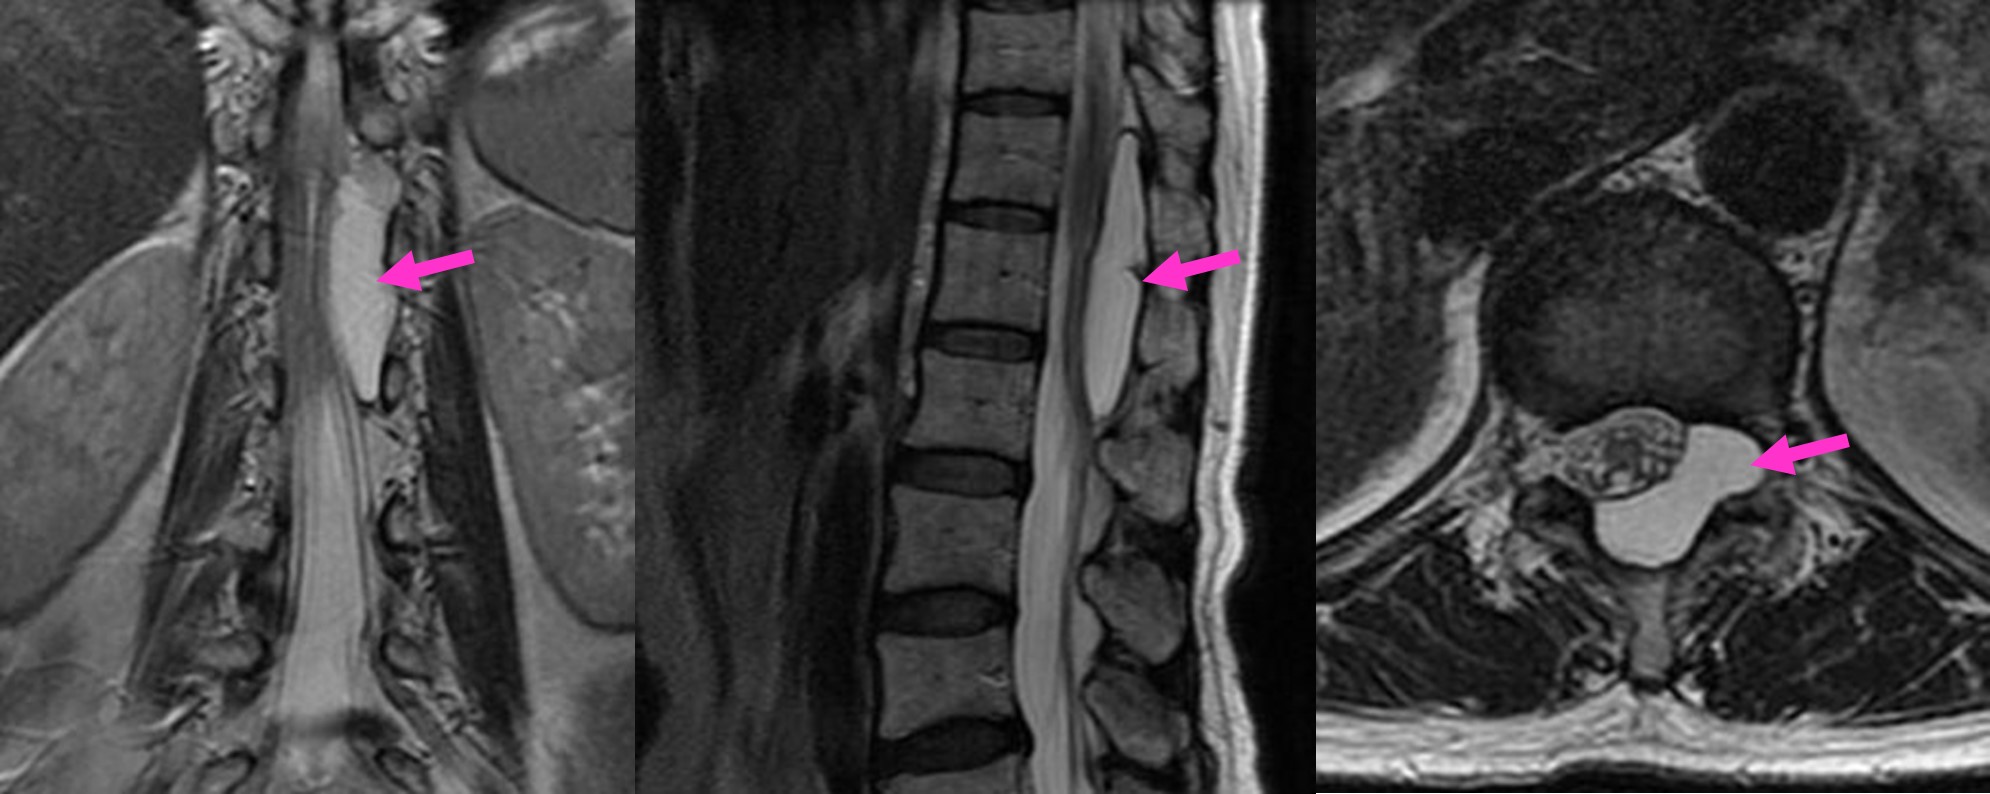

図 胸椎にできたくも膜のう腫(矢印)。小さい切開による内視鏡を併用した最小侵襲手術で症状は劇的に改善しました。